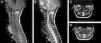

Caso clínicoPresentamos un caso excepcional de mielopatía por compresión a nivel del atlas en un niño de 5 años con síndrome de Down provocado por una anomalía del desarrollo del arco posterior de C1. Se realizó una laminectomía posterior a ese nivel con mejoría de la sintomatología previa.

Case reportWe report an exceptional case of myelopathy due to compression at the level of the atlas in a 5-year-old boy with Down syndrome provoked by a developmental anomaly of the posterior arch of C1. A posterior laminectomy was achieved at that level with improvement of the previous symptoms.